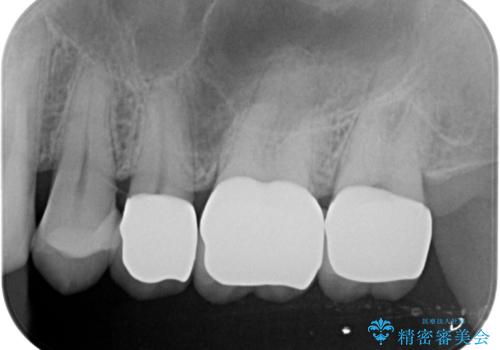

銀歯を丁寧に除去すると、銀歯の下で虫歯の再発やセメントの劣化が確認されたので、拡大鏡・マイクロスコープを用いて虫歯のみを丁寧に取り除いたのち、精密なセラミッククラウンの製作を進めます。

拡大鏡・マイクロスコープを用いて虫歯を丁寧に除去することで、健全な歯質や神経を守ることにつながります。